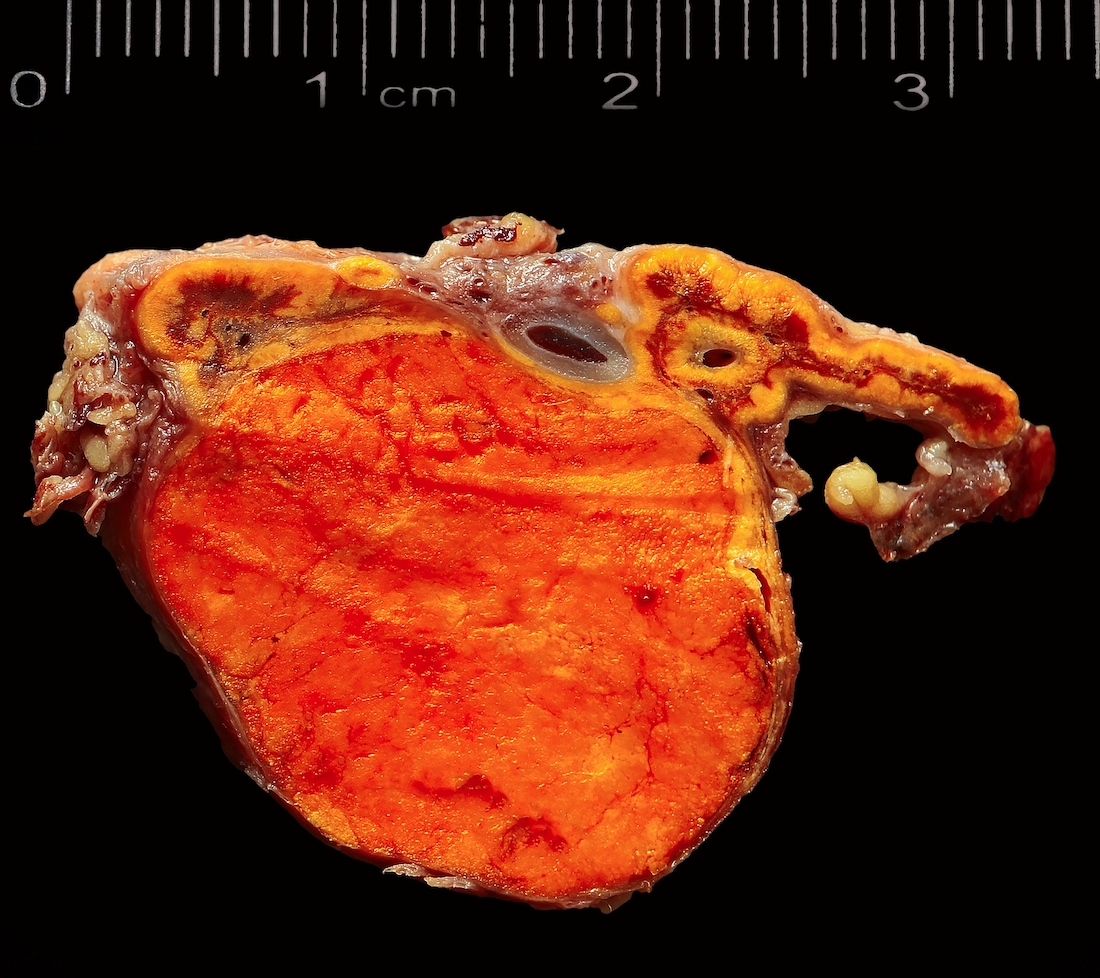

Gross description

- Weight usually < 50 grams (in pediatric patients may weight up to 500 grams) (Mod Pathol 2011;24:S58)

- Size usually < 5 cm

- Unilateral, solitary, golden yellow

- May have focal dark areas corresponding with hemorrhage, lipid depletion, increased lipofuscin

- Functional adenoma may result in atrophy of ipsilateral or contralateral adrenal cortex

Gross images